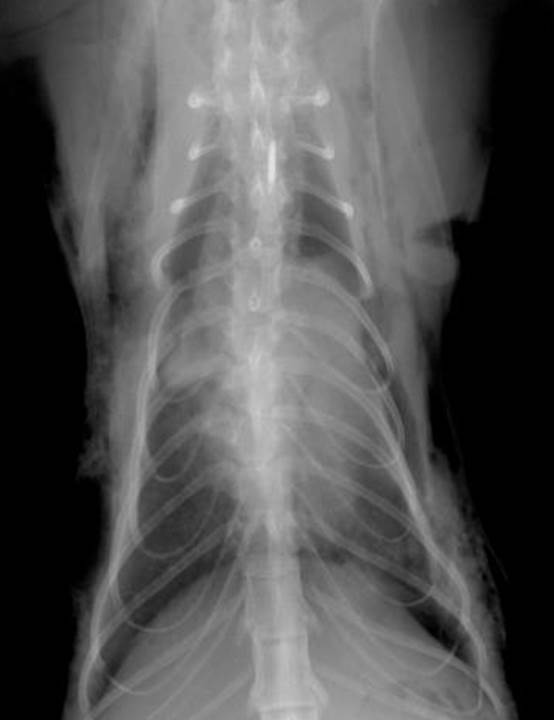

What changes are seen when pleural fluid occurs?

you see a number of changes – fluid in pleural cavity, separating lungs from thoracic wall, soft tissue fluid opacity – see it ventrally and dorsally. If lying on side, fluid drops to bottom and then spread up the sides slightly, separates lungs from spine and sternum – get rounding up, scalloping of lung edges ventrally, see bits of fluid going in between lung lobes. Also due to this fluid, get border obliteration of Cardiac Silhouette